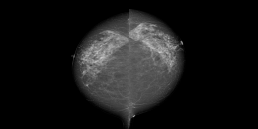

Patiente de 69 ans sans antécédent personnel ou familial de cancer du sein ou de l’ovaire, adressée pour une mammographie de dépistage systématique.

Les seins sont denses de type C selon la classification BI-RADS.

Il y a eu un doute sur une zone de distorsion architecturale très difficilement visualisée sur l’imagerie 2D sans l’aide de l’IA sur une seule incidence : cette image aurait pu passer inaperçue dans le flux patient de la vacation.

MammoScreen a cependant bien repéré cette anomalie sur les 2 incidences avec un score de forte suspicion à 9.

Un cliché de tomosynthèse et une échographie sont réalisés au décours, permettant de confirmer la présence d’une masse atténuante et de contours irréguliers classée ACR5 à l’union des quadrants externes du sein droit, à 9h 3 cm et mesurant de 8x7x8 mm.